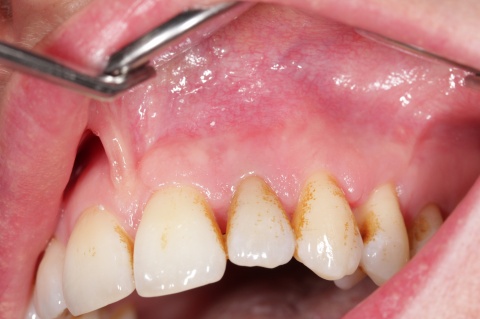

Im Januar 2019 stellte sich ein 52-jähriger Soldat mit einem auf Gingivaniveau abgebrochenen Zahn 21 im Rahmen einer Notfallbehandlung bei uns vor. Zur Wiederherstellung der Ästhetik, Phonetik und Beißfunktion wurde die Krone in direktem Verfahren wieder aufgebaut. Das anschließend angefertigte Röntgenbild zeigte eine zu kurze und inhomogene Wurzelfüllung mit Hinweisen auf eine vorliegende Via falsa.

Gleichzeitig berichtete der Patient über Beschwerden am Zahn, welche wiederholt auftraten und sich durch Druck auf das Vestibulum reproduzieren ließen. Eine Schwellung, Fistelung oder erhöhte Sondierungswerte lagen zu diesem Zeitpunkt nicht vor. Da zur Aufnahme einer laborgefertigten Restauration eine vorherige Stiftinsertion geplant war, vereinbarten wir zunächst die Revision der vorhandenen insuffizienten Wurzelfüllung. Trotz Dentalmikroskop und vorgebogenen Ultraschallfeilen ließ sich der ursprüngliche Kanalverlauf während der Revisionsbehandlung nicht mehr darstellen (Abb. 3 zeigt den Verlauf der Via falsa).

Bei der Kontrolle zwei Monate später war die Patientin vollkommen beschwerdefrei und die Fistelung ausgeheilt. Lediglich die Verfärbungen in Folge der unterstützenden chemischen Reinigung mit einem chlorhexidinhaltigen Präparat empfand die Patientin als ästhetisch störend.

Zähne resultierten aus der Anwendung eines chlorhexidinhaltigenhaltigen

Präparates.